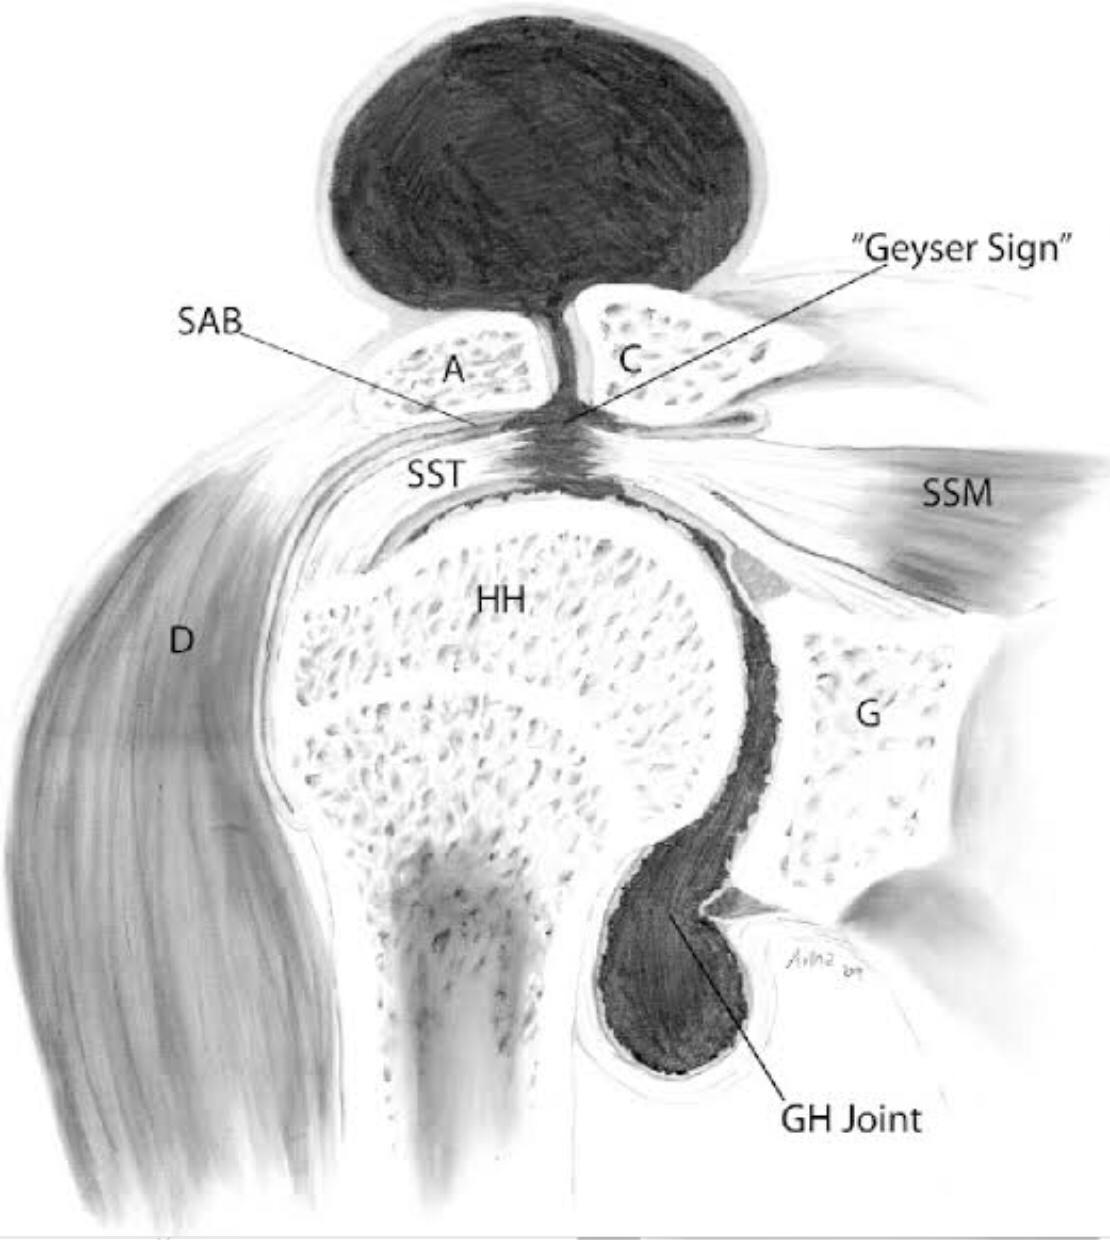

The geyser sign is a subcutaneous pseudotumor above the acromioclavicular joint, also known as AC joint cyst. The geyser sign is an infrequently encountered imaging sign that was originally described on conventional fluoroscopy-guided shoulder arthrography. The first case report of these cysts occuring in association with rotator cuff tears was made by Dr. Edward Craig in 1984, and again in 1986. The sign derives its name from its geyser-like appearance.

On physical examination, an AC joint cyst is a palpable fluid-filled mass. MRI scanning or a shoulder arthrogram should be obtained to evaluate the shoulder. Unenhanced MRI scans showing a large rotator cuff tear, a degenerated AC joint, and a large subcutaneous cyst adjacent to the AC joint is virtually patognomonic for the disease. Contrast administration on MR arthrogram will show the synovial fluid or intra-articular contrast extravasates from the glenohumeral joint into the subacromial bursa, into the AC joint, and then into an overlying cystic mass when a full-thickness rotator cuff tear is present, resembling a geyser spouting upwards.